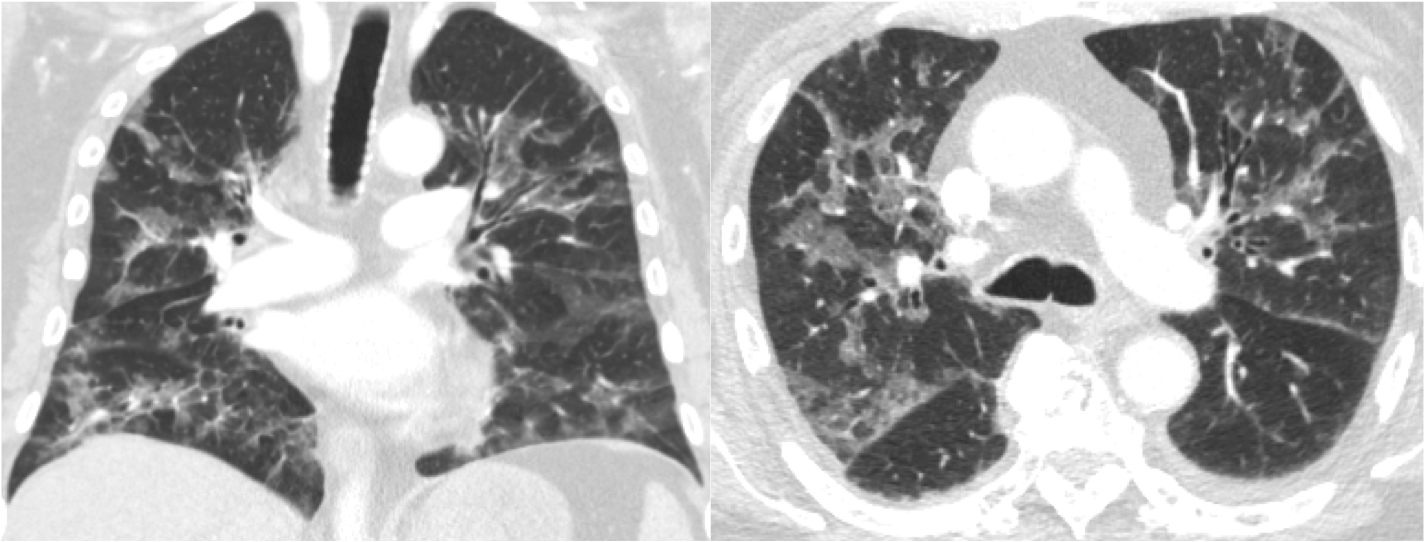

Figure 1Case 1: Coronal and axial computed tomography scans of the chest after administration of contrast demonstrate bilateral ground-glass opacities with associated septal thickening, the absence of pleural effusion, and no hilar adenopathy.

A 75-year-old male presented with metastatic hormone-sensitive prostate cancer. He underwent treatment with leuprolide, abiraterone acetate, and prednisone 5 mg twice daily for 1.5 years until his cancer became castrate resistant. He was subsequently started on enzalutamide, and abiraterone acetate and prednisone were discontinued. Six months later, he developed back pain and weakness in his upper extremities. Magnetic resonance imaging (MRI) of the thoracic spine was performed, revealing a metastatic tumor circumferentially involving the spinal cord from thoracic vertebrae 3 to 5. He was started on 8 mg dexamethasone twice daily and referred to radiation oncology for definitive treatment. He was maintained on this steroid regimen throughout his radiation therapy. During the course of radiation therapy, he developed some left eye irritation for which he was prescribed ofloxacin drops. He also developed a dry cough initially thought to be radiation pneumonitis. He was maintained on 8 mg dexamethasone twice daily (>100 mg prednisone equivalent/day) for a total of 49 days, at which point he was tapered to 4 mg twice daily. Three days into the steroid taper, he was febrile (temperature up to 102° F), hypotensive with a new oxygen requirement, and had diarrhea. He was admitted to the hospital and found to have norovirus gastroenteritis. Additionally, a direct fluorescent antibody test was positive for Pneumocystis jirovecii. He also had elevated lactate dehydrogenase and (1,3)-beta-D glucan levels. A computed tomography (CT) scan of the chest demonstrated diffuse bilateral ground-glass opacities (Figure 1). Despite maximum medical treatment, the patient’s respiratory status continued to decline and he was ultimately transitioned to comfort care, succumbing to PCP and its subsequent complications. During hospitalization, it was discovered that he had herpes zoster virus keratitis in his left eye; thus, his cough and eye irritation were in retrospect the first signs of his compromised immune status.

In patients without HIV infection presenting with respiratory complaints, there is a longer time to diagnosis of PCP and this is an independent risk factor for death.13 Patients with solid tumors are at risk for common causes of pulmonary processes, but Pneumocystis jirovecii should remain on a provider’s differential diagnosis in the appropriate situation. When considering PCP as a differential diagnosis, a thorough review of the patient’s clinical course, medications, and imaging should be done. Imaging can often be nonspecific with perihilar and mid-to-apical predominant ground-glass opacities on radiography and CT. When determining whether a pulmonary infiltrate is PCP versus radiation pneumonitis, it is important to recall that radiation pneumonitis is a more geographic finding with confluent ground-glass opacities that are confined to the path of radiation. For PCP, pneumatoceles without pleural effusion and lymphadenopathy can be seen in 30% of cases.21